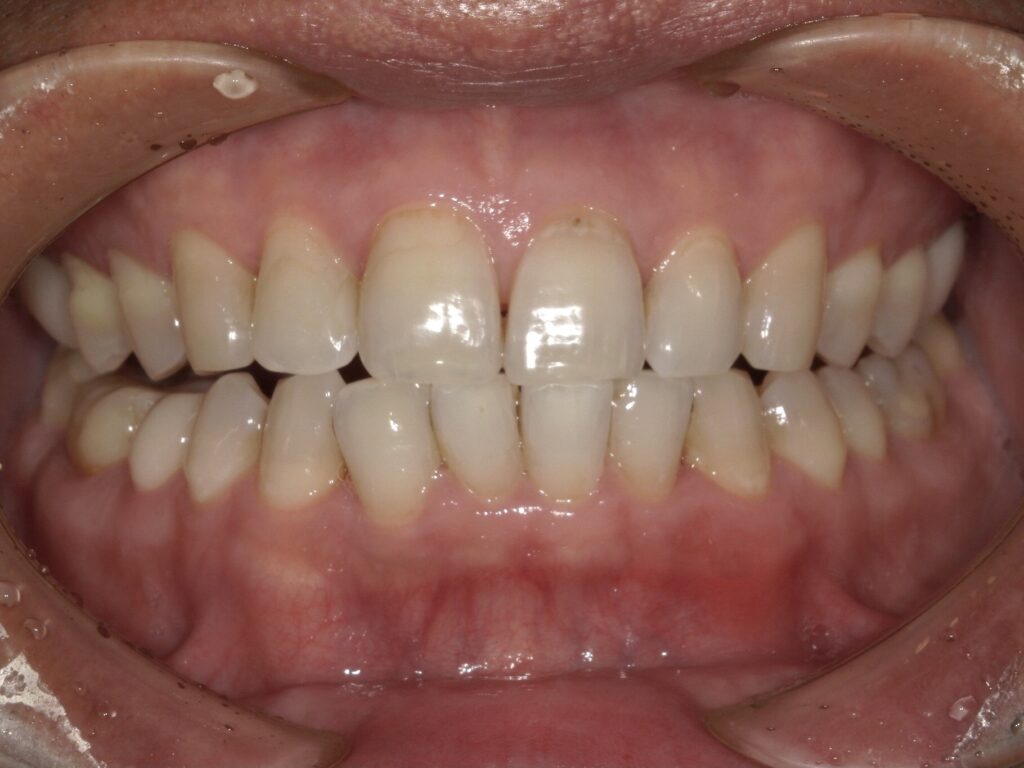

【B様】

Before

After

年齢 | 40代後半 |

性別 | 男性 |

主訴 | 黄ばみが気になるため白くしたい |

施術内容 | オフィスホワイトニング3回 |

治療期間 | 2週間 |